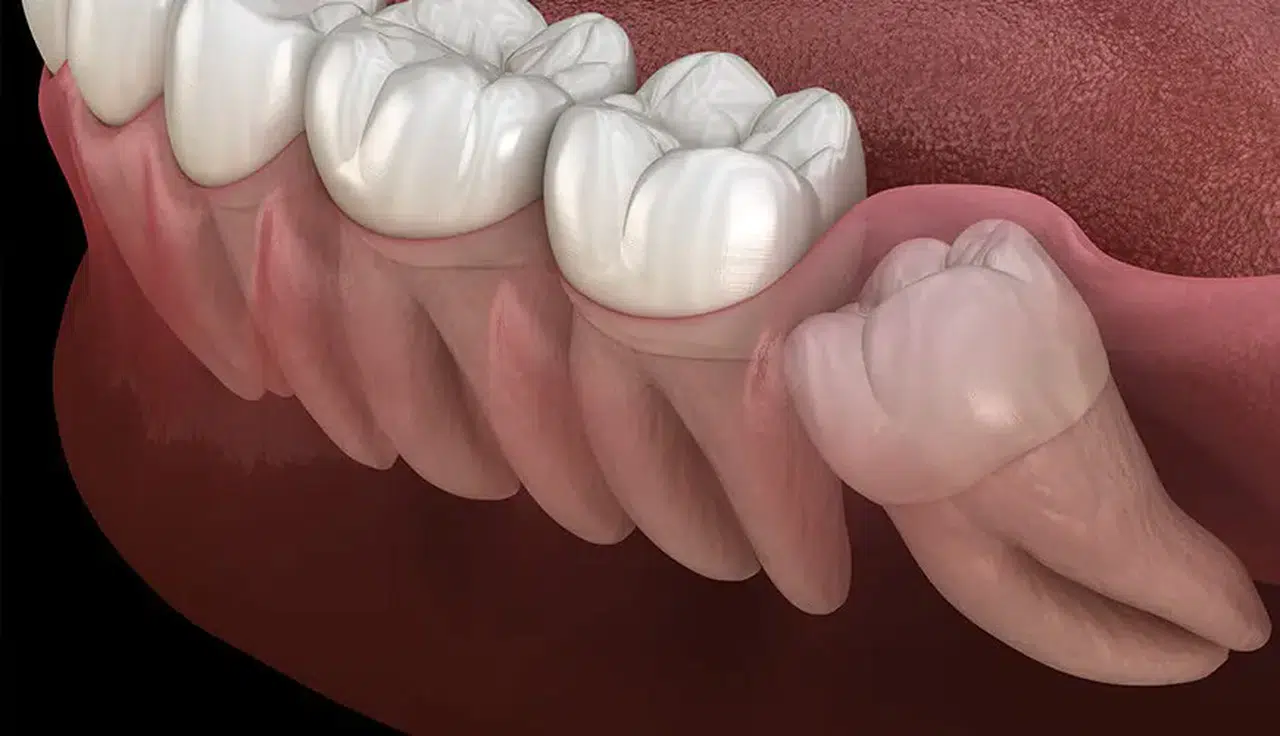

Yan yatmış şekilde kalan 20 yaş dişleri öndeki dişlere baskı yapar. Bu durum özellikle gençlerde dişlerde çapraşıklık, sıkışma ve ortodontik bozukluklara yol açar. Ortodontik tedavi görmüş kişilerin dişlerinin tekrar bozulmasına sebep olabilir.

4. Dişlerde Sıkışma ve Çapraşıklık

Yan yatmış şekilde gömülü kalan 20’lik dişler, öndeki dişlere baskı yaparak çapraşıklık, dişlerin öne doğru itilmesi ve ortodontik bozulmalara sebep olabilir.